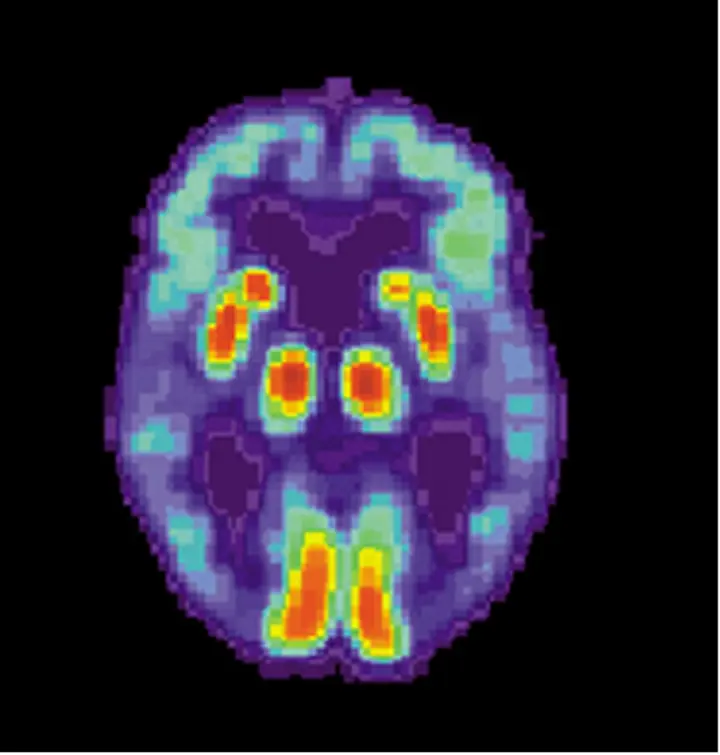

عادة ما يبدأ مرض الزهايمر بصمت، مع تغيرات في الدماغ تبدأ قبل سنوات من ملاحظة أي شخص للمشكلة. عندما يكون الشخص العزيز عليك في هذه المرحلة المبكرة، لن يكون لديه أي أعراض يمكنك اكتشافها. وفقط التصوير المقطعي بالإصدار البوزيتروني، وهو اختبار تصوير يوضح كيفية عمل الدماغ، يمكن أن يكشف ما إذا كان لديهم مرض الزهايمر. ومع انتقالهم إلى المراحل الستة التالية، سيرى صديقك أو قريبك المصاب بمرض الزهايمر المزيد والمزيد من التغييرات في تفكيره ومنطقه.